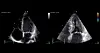

FORSKJELLER: Ultralydbilde av et normalt hjerte til venstre og hjertet hos en eldre kvinne med høyt blodtrykk til høyre. Begge bildene er fra slutten av tømningen for å demonstrere hvordan ventrikkelen hos hypertonikeren tømmer seg nærmest fullstendig. Legg også merke til forskjellene i veggtykkelse og atriumstørrelse. Foto: Illustrasjon: Johannes Soma

Ved konsentrisk venstre ventrikkelhypertrofi med liten kavitet kan EF > 70 prosent være nødvendig for å sikre et normalt minuttvolum i hvile (3). Den kardiale reserven er begrenset, både på grunn av at ventrikkelen fylles langsomt og ettersom den tømmer seg nærmest fullstendig i hvile.

HJERTESVIKT. Høyt blodtrykk og aldring fører til redusert elastisitet i ventrikkelen på grunn av økt muskel- og bindevev. Sugeevnen og langaksefunksjonen reduseres (6). I tillegg svekkes funksjonen av forsinket myokardrelaksasjon og endringer i ventrikkelens geometri med økning av veggtykkelsen og reduksjon av kaviteten (3–5).

Ved hypertensiv hjertesykdom kan hjertefunksjonen se tilfredsstillende ut dersom en er av den oppfatning at jo høyere EF, desto bedre. Geometriske forandringer i venstre ventrikkel og atrium og endringer i fyllingsmønsteret er illustrert i figur 1 og 2, publisert i Dagens Medisin 12/2015. Andre ekkokardiografiske tegn til økte atrie-/fyllingstrykk er: Økt ratio av strømningshastigheten i tidlig fyllingsfase og den tilsvarende hastigheten i myokard (e/e’), dilatasjon av venstre atrium og lungevener, bevegelsen av atrieseptum, endring av strømningsmønsteret i lungevenene og pulmonal hypertensjon (2). ProBNP er dessuten en nyttig indikator på atrietrykket (4).